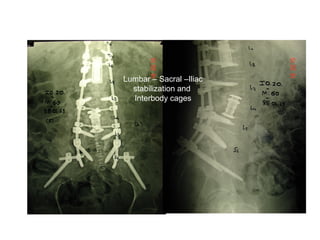

Late post operative destabilization

due to vertebral collapse

Lumbar – Sacral –Iliac

stabilization and

Interbody cages